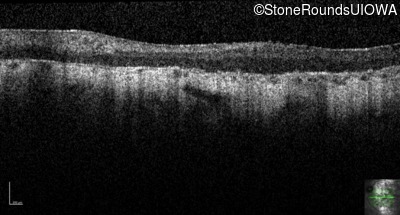

Age at visit: 33 years